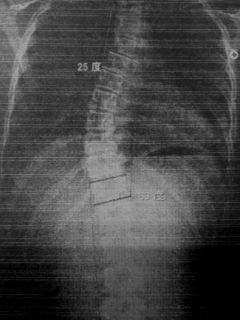

レントゲンのビフォーアフター)

写真1(施術前) 写真2(5か月後)

○コブ角上27度⇒25度(2度改善)、下40度⇒33度(7度改善)

※コブ角は専門医の診断